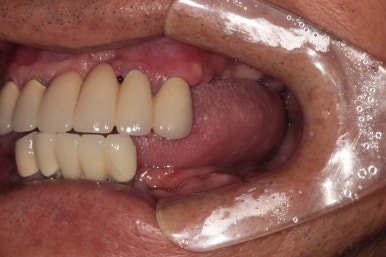

정면에서 찍은 구강 내 사진입니다.

대부분의 치아가 크라운으로 씌워져 있으셨어요. 아무래도 보철물이 너무 많다보니, 구강위생관리가 쉽지 않으신 상태였습니다.

측면 사진입니다.

먼저 왼쪽 사진이 환자분의 우측 사진인데요, 아래턱 어금니 부위는 이미 치아가 없어진지 오래되어 깔끔하게 나은 잇몸상태를 볼 수 있었습니다.

위쪽은 치석이 너무 많았습니다. 만성 치주염이 심하신 상태였죠..

오른쪽 사진이 환자분의 좌측 사진입니다. 여기서 잘 안보이실 수 있지만, 왼쪽 아래 송곳니 부위에 잇몸 속 고름이 잔뜩 차서.. 흔들흔들한 상태였어요.